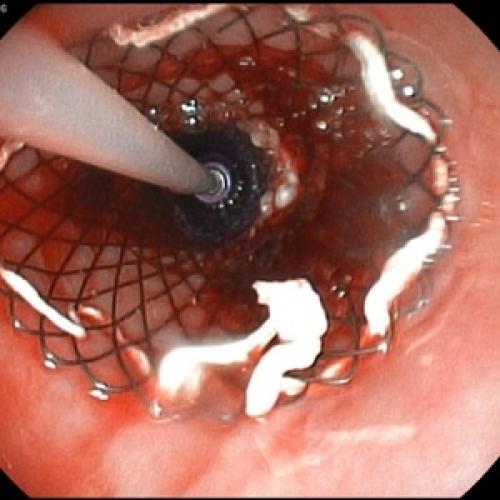

Отсутствие эффекта от проводимой анальгетической и спазмолитической терапии в течение 12-48 часов, быстро прогрессирующая желтуха, отсутствие желчи в ДПК при ЭГДС, признаки билиарной гипертензии по данным УЗИ свидетельствуют о стеноза терминального отдела холедоха (вклиненный конкремент БДС, папиллит). В этом случае показано проведение ЭПСТ. При остром панкреатите ЭПСТ производится без ЭРХПГ!